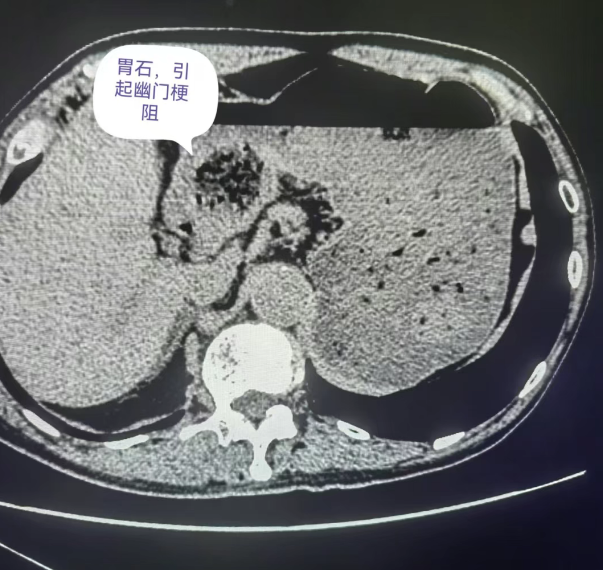

胃結(jié)石在初期可能沒有明顯癥狀,最多讓人感覺有點(diǎn)上腹部不適或者飽脹,很容易被忽略。但隨著它慢慢長大,就開始“興風(fēng)作浪”。腹痛是最常見的癥狀之一,疼痛程度不一樣,有的是隱隱作痛,有的則是脹痛,甚至劇烈疼痛。還會出現(xiàn)惡心、嘔吐的情況,要是結(jié)石損傷了胃黏膜,還可能引發(fā)嘔血、黑便。更嚴(yán)重的,胃結(jié)石可能導(dǎo)致幽門梗阻,讓食物無法正常通過,那可就麻煩大了。幽門梗阻發(fā)生時(shí),食物和胃液無法順利進(jìn)入小腸進(jìn)行消化和吸收,大量積聚在胃內(nèi),導(dǎo)致胃內(nèi)壓力升高,引發(fā)嚴(yán)重的嘔吐。患者會頻繁嘔吐出大量酸臭的胃內(nèi)容物,且嘔吐后癥狀也難以緩解,還可能伴有脫水、電解質(zhì)紊亂等嚴(yán)重并發(fā)癥。

在胃結(jié)石的 CT 影像中,不同類型的結(jié)石有著獨(dú)特的“長相”。當(dāng)胃內(nèi)存在植物性結(jié)石時(shí),其影像表現(xiàn)通常為形狀不太規(guī)則的低密度影。仔細(xì)觀察,能看到內(nèi)部有散在分布的點(diǎn)、條狀稍高密度影,這是植物纖維的影像特征。若是混合性結(jié)石,CT影像則更為復(fù)雜,既有低密度的植物成分區(qū)域,又有因鈣化或其他礦物質(zhì)沉積形成的高密度區(qū)域,密度不均勻,邊界也相對模糊。例如:在一些長期存在的胃結(jié)石中,由于鈣鹽的不斷沉積,結(jié)石內(nèi)部會出現(xiàn)鈣化灶,在CT影像上表現(xiàn)為高密度影,與周圍低密度的植物成分形成鮮明對比。

而CT增強(qiáng)掃描在胃結(jié)石診斷中也有特殊意義。對于一些與胃壁關(guān)系密切、難以判斷是否侵犯胃壁的結(jié)石,增強(qiáng)掃描能清晰顯示胃壁各層結(jié)構(gòu)。正常胃壁在增強(qiáng)后呈現(xiàn)均勻強(qiáng)化,若結(jié)石周圍胃壁強(qiáng)化異常,如局部增厚、強(qiáng)化程度改變,就提示胃壁可能受到了結(jié)石的刺激或損傷,幫助醫(yī)生更準(zhǔn)確評估病情嚴(yán)重程度,為后續(xù)治療方案的制定提供更可靠的依據(jù)。當(dāng)胃壁受到結(jié)石刺激發(fā)生炎癥時(shí),在增強(qiáng)掃描圖像上,炎癥部位的胃壁會出現(xiàn)增厚、強(qiáng)化程度增加的表現(xiàn),這表明該區(qū)域的血供增加,是炎癥反應(yīng)的典型特征。醫(yī)生通過觀察這些變化,可以判斷胃壁炎癥的范圍和程度,從而選擇合適的治療方法,如是否需要使用抗生素進(jìn)行抗感染治療,或者是否需要及時(shí)進(jìn)行手術(shù)干預(yù)。